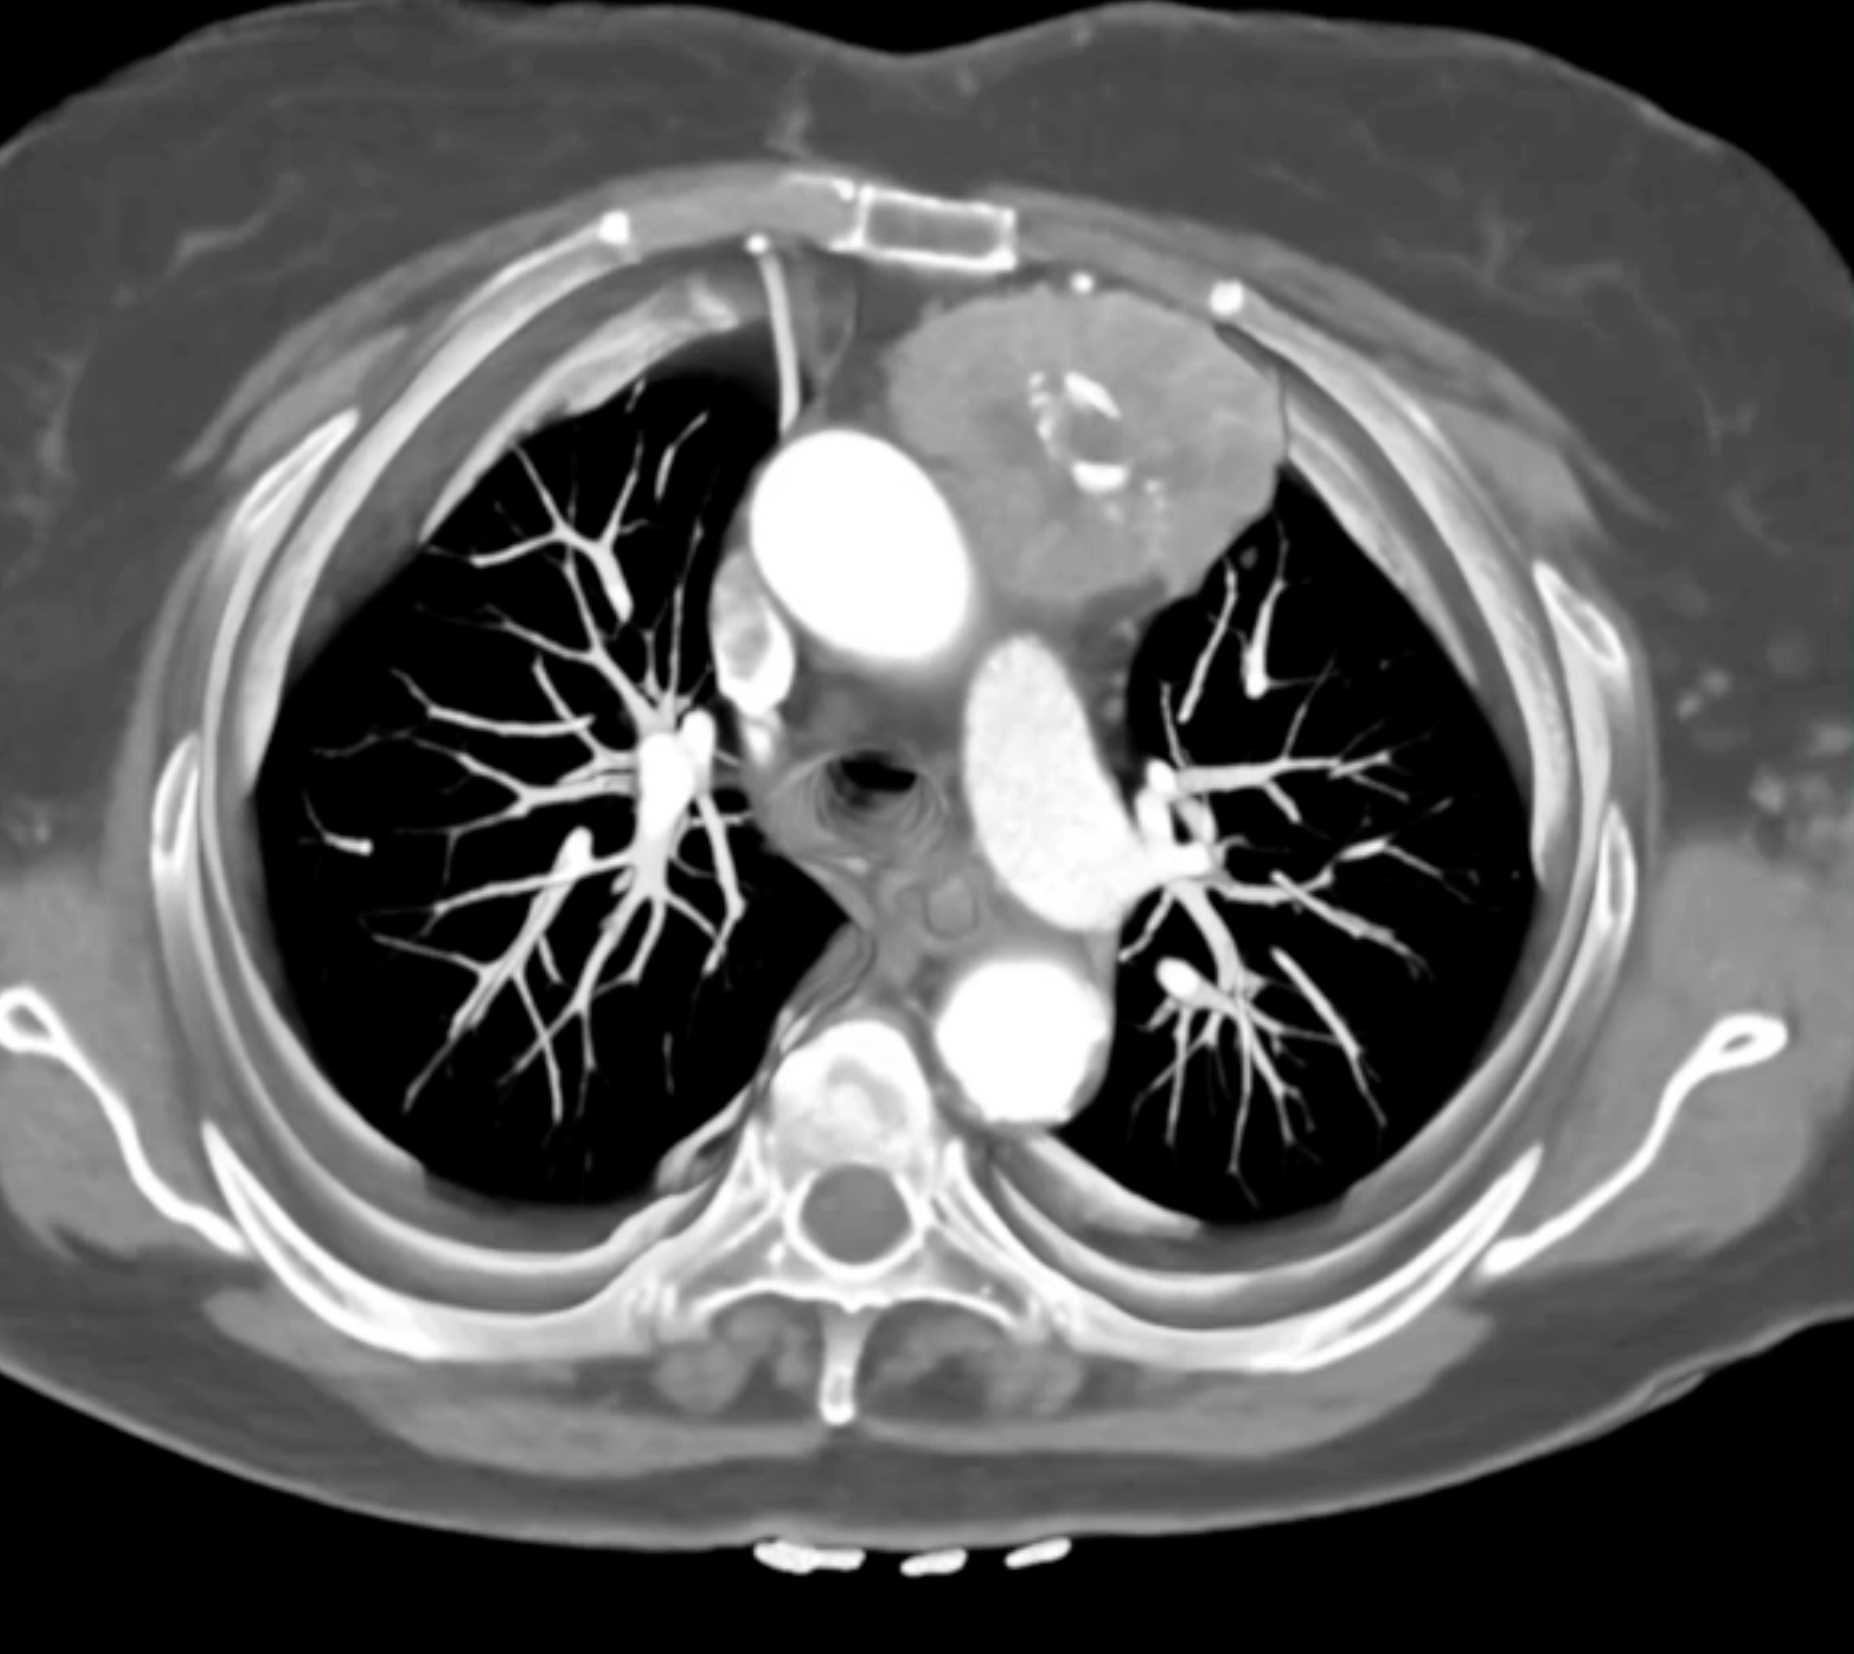

Thymic Carcinoma